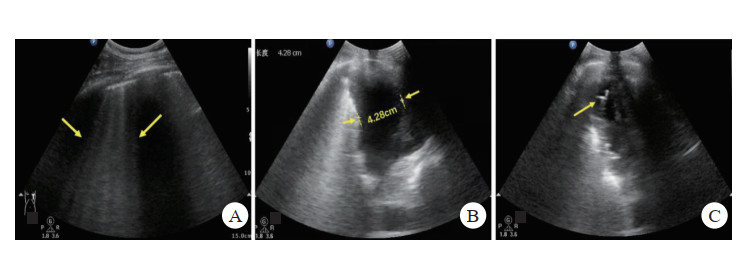

(2)血胸:如坐位扫查,仅肋膈角被无回声积液充填,为少量积液;如任意体位胸腔均可见液性暗区,为中-大量积液,超声对其诊断准确性100%[39](图 7-B)。

2.3.3 检查方法采用BLUE法中的检查位置(见图 7)。共6个检查点:(1)上BLUE点位于上面手的中央(左侧、右侧共2个);(2)下BLUE点位于下面手掌的中央(左侧、右侧共2个)。这四个点遵循肺部解剖,尽可能避开了心脏;(3)后侧肺泡或胸膜综合征点(posterolateral alveolar and/or pleural syndrome point, PLAPS)位于下蓝点延长线与腋后线相垂直的交点;(4)膈肌点(diaphragmatic point)位于下蓝手小指外侧缘即膈肌线,其延长线与腋中线交点。检查时间一般不超过3 min。

检查时间一般不超过3 min。

| A: 上蓝点(2个)、下蓝点(2个);B:PLAPS点(黄箭)、膈肌点(蓝箭) 图 7 BLUE法定位扫查 |